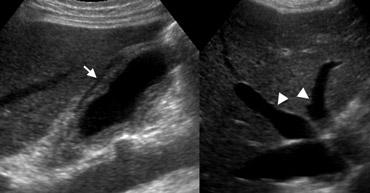

Bên trái là nam giới 75 tuổi bị viêm gan do thuốc.

Hình siêu âm cắt dọc của túi mật không căng giãn cho thấy dày thành lan tỏa (mũi tên), và sỏi túi mật tình cờ phát hiện có thể gây nhầm lẫn trong chẩn đoán.

Bên trái là nam giới 74 tuổi bị suy tim phải sung huyết.

Siêu âm cho thấy dày thành lan tỏa của túi mật không có sỏi và không đau, kèm theo các tĩnh mạch gan (đầu mũi tên) và tĩnh mạch chủ dưới giãn lớn, là bằng chứng hỗ trợ chẩn đoán suy tim phải.